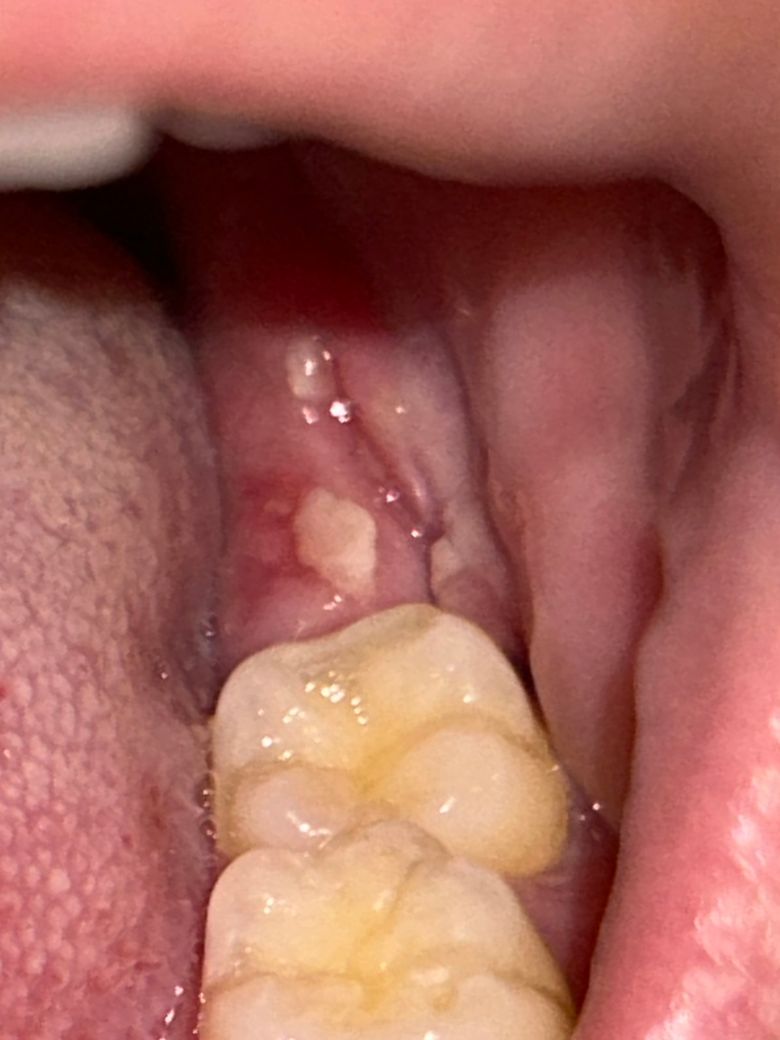

사랑니 실밥 제거 후 잇몸 벌어졌는데 괜찮은건가요?

화요일에 사랑니 뽑고 진통제를 먹어도 통증이 너무 심해서 목요일에 병원에 가서 실밥을 풀었더니 통증이 사라졌습니다. 결국 일주일이 지나지 않았을 때 빠르게 실밥 제거를 했는데 잇몸이 벌어졌습니다. 이거 괜찮은거 맞나요…? 다시 붙지는 않는건가요?

• 2번 째 사진

사랑니 실밥 제거 후에는 잇몸이 약간 벌어져있는 것이 보통이며 사진상 문제는 없어보입니다.

아직 사랑니가 다 아물지 않아서 그렇습니다. 시간이 지나면서 잇몸이 아물면 괜찮아 지니 너무 걱정하지마세요.

사랑니를 발치한 후 실밥을 풀고 잇몸이 벌어져도 크게 문제가 되진 않습니다. 대부분 시간이 지나면서 아물기 때문에 해당 부위가 자극되지 않도록 하는 것이 좋습니다.